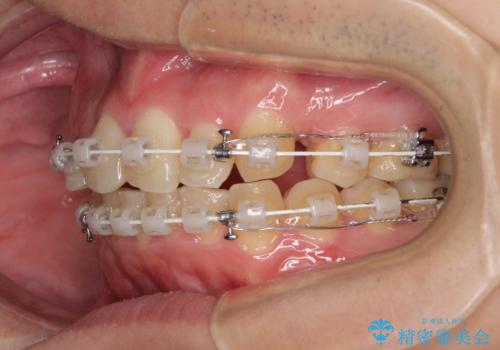

- 矯正装置

- 審美装置

- 治療計画

- 結婚式が近いとのことで、前歯のデコボコを改善したいと来院された患者様です。

口元の突出感はないものの、上顎前歯のデコボコが著しかったため、上顎左右第一小臼歯2本を抜歯することとしました。

咬合力が非常に強く、抜歯したスペースがなかなか閉じないであろうことは予想できましたが、思っていた以上に期間がかかりました。

前歯のすり減りも著しかったため、仕上げの位置の調整にも期間を要しました。